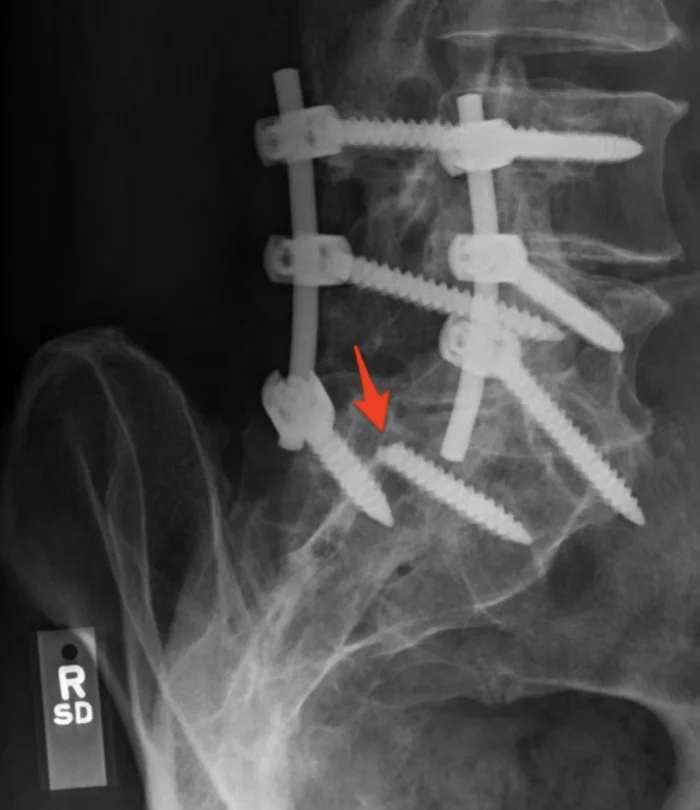

4. Один из винтов, фиксирующих мой позвоночник, выпал

Я сидел за столом, когда почувствовал (и услышал) резкий щелчок в спине. Почти сразу же я утратил чувствительность в левой ноге.